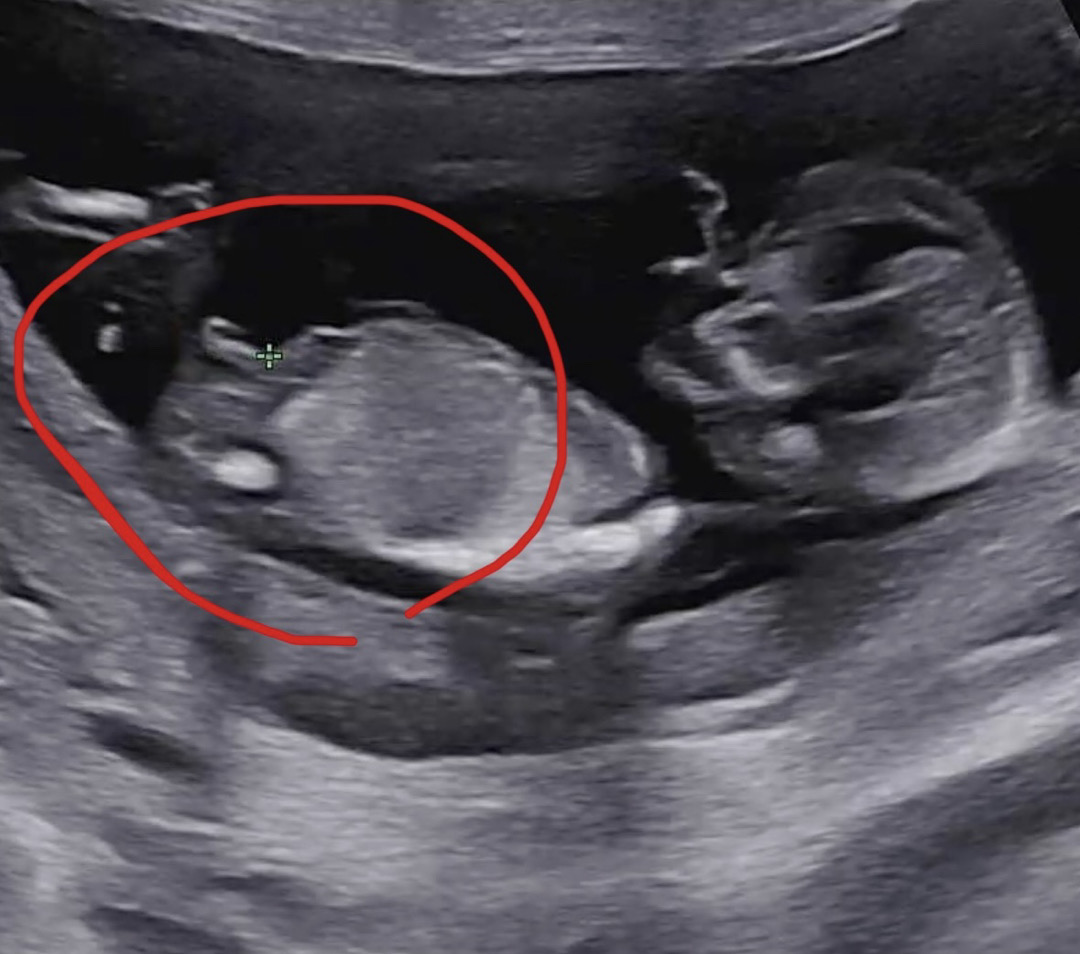

둘째 성별 각도법 질문입니다!!

둘째라서 더 궁금한것같아요 ㅎㅎㅎ 각도법으로 보면 어떻게 보이시나요?